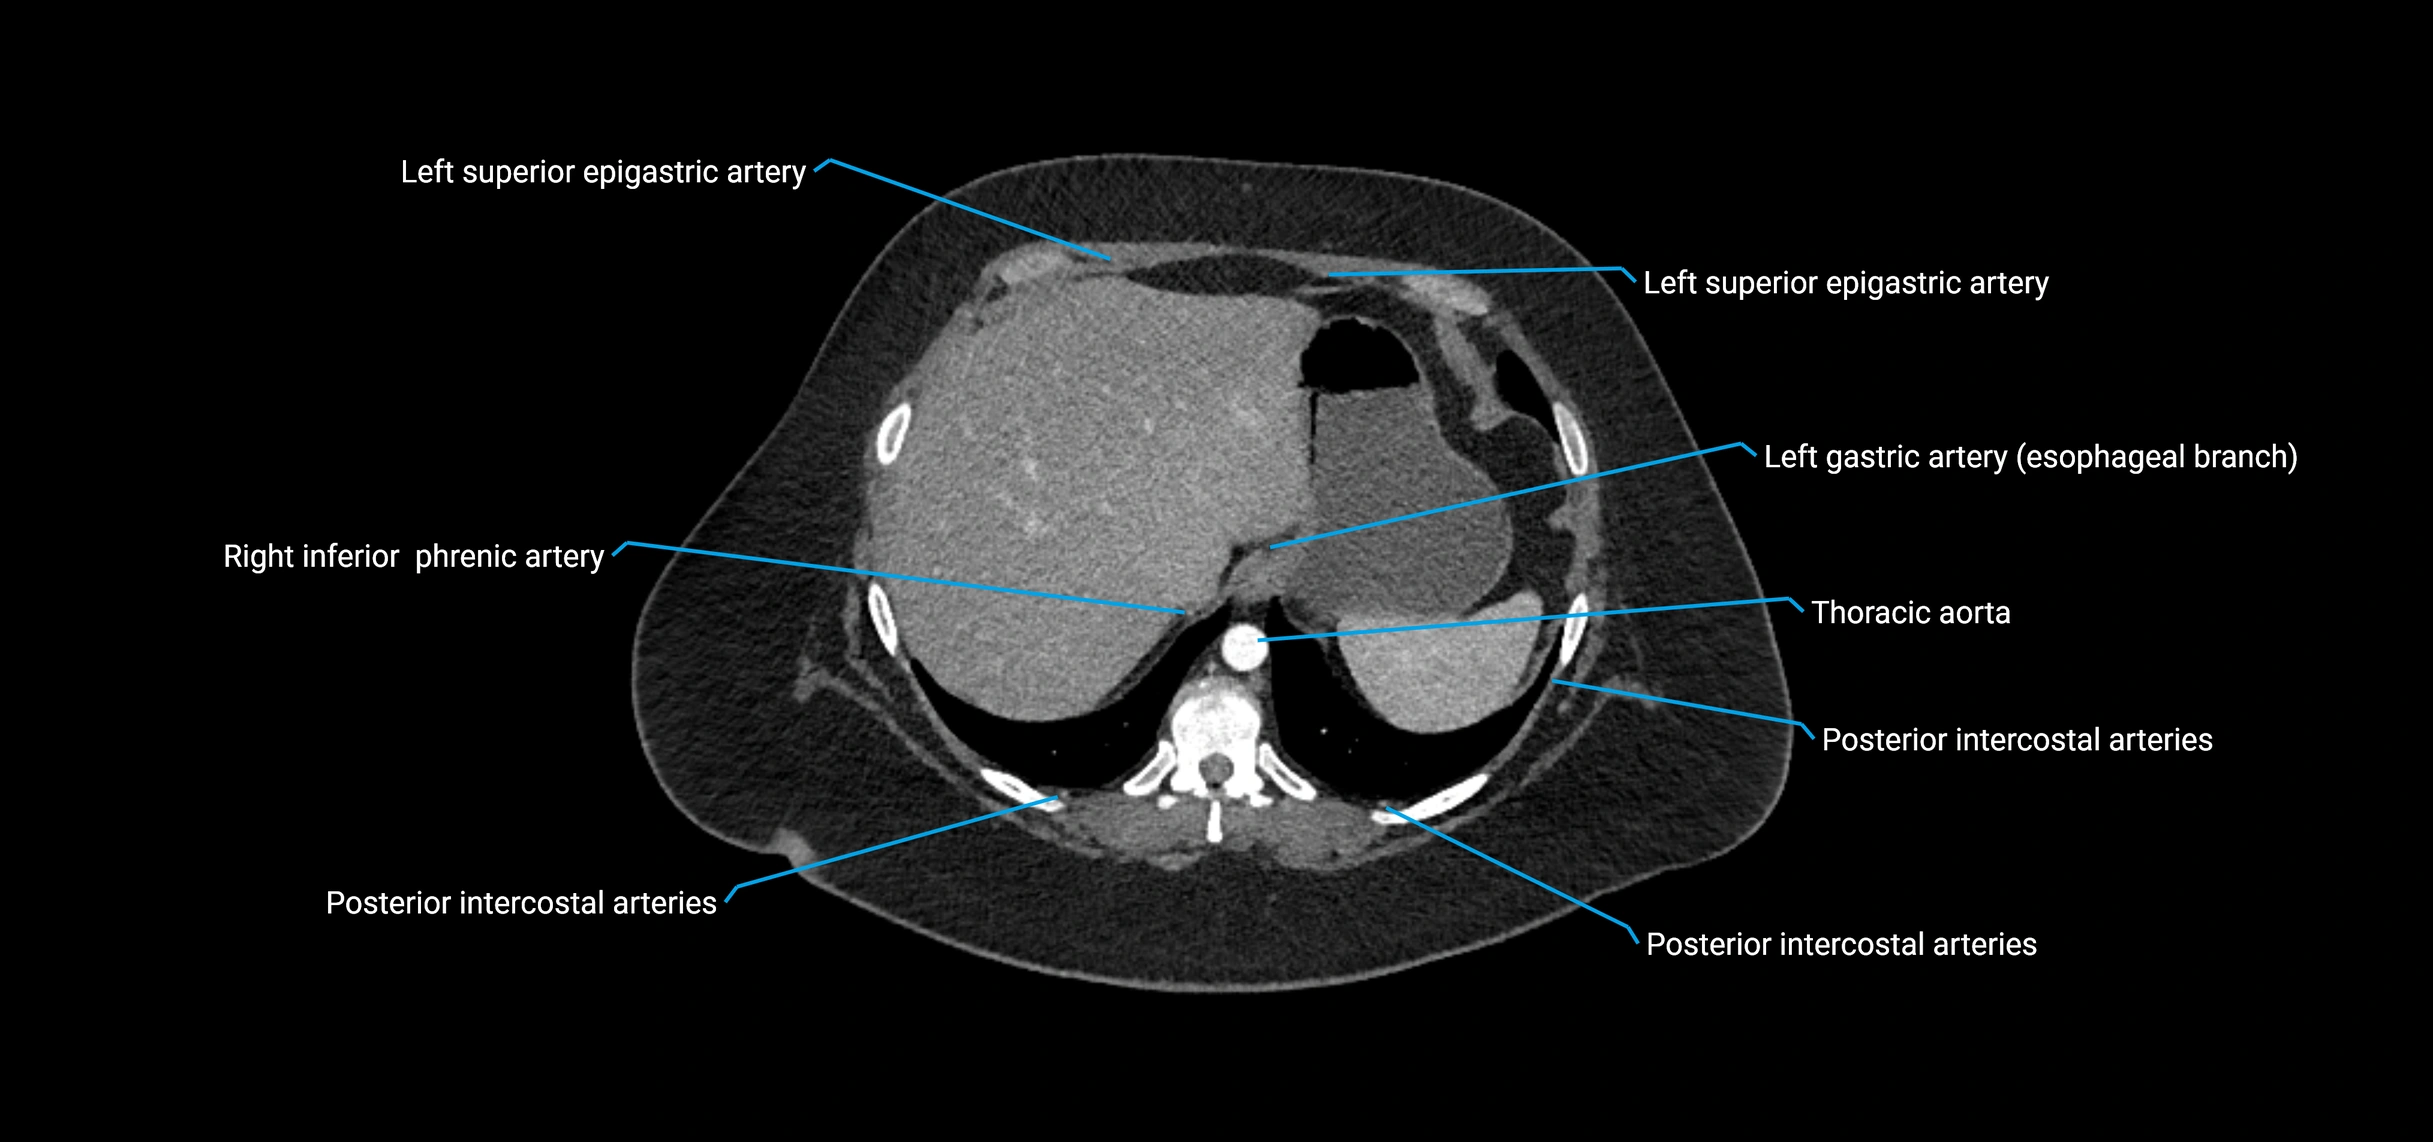

CT images

image